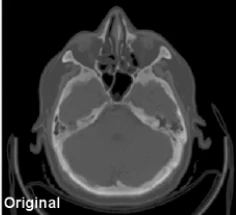

Processamento avançado de TC com redução significativa de ruído e melhoria da qualidade da imagem para diagnósticos mais precisos, permitindo protocolos de baixa dose sem comprometer a qualidade.

Original

Processado com iRAD